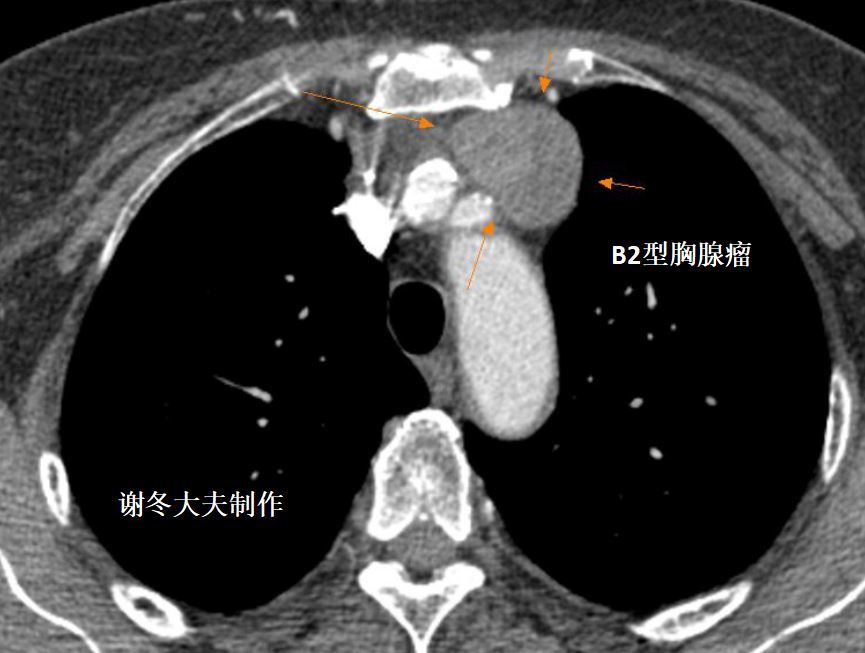

2.侵袭性胸腺瘤

侵袭性胸腺瘤明确的CT征象:纵隔结构的包绕,直接侵犯中心静脉、心包或胸膜种植转移和晚期发生的跨膈肌扩散。

1.多数胸腺瘤是低度恶性肿瘤,但少数胸腺瘤表现为侵袭性病变,可以侵犯大血管,包括无名动脉,上腔静脉,肺动脉等,也可以出现转移,包括胸腔内转移,肺转移,胸膜转移,锁骨上淋巴结转移,甚至脑转移,骨转移等。